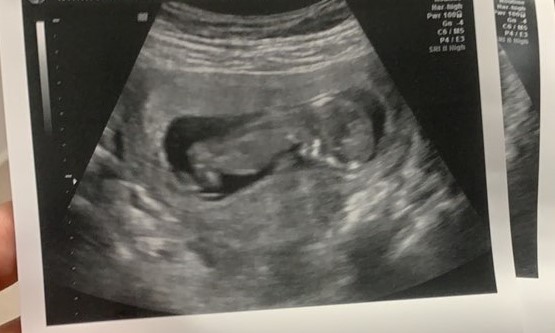

There, Annemarie received an ultrasound and saw the beating heart of her six-week preborn child. The abortion pill had still not completed its purpose.